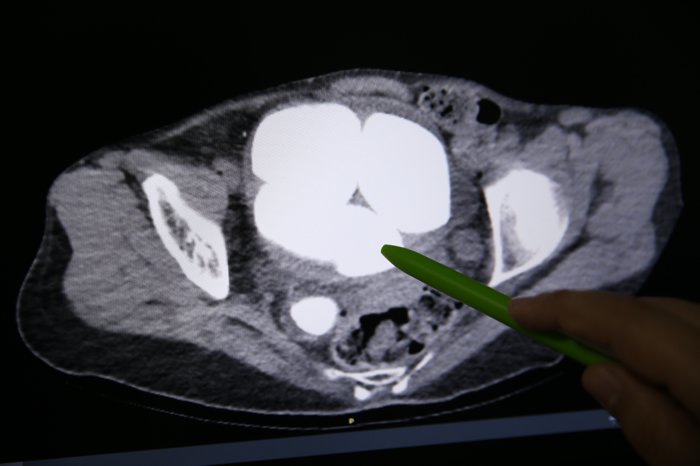

Üroloji Bölümünde Opr. Dr. Süleyman Çankaya tarafından yapılan tetkiklerde, hastanın mesanesi ve idrar kanalında en küçüğü 2, en büyüğü 9 santimetre olan 6 taş tespit edildi.

Çankaya ve Opr. Dr. Yekta Bıçak'ın geçen hafta gerçekleştirdiği cerrahi müdahale ile hastanın idrar kanalı ve mesanesinde bulunan farklı ebatlardaki 6 taş yaklaşık 1,5 saat süren operasyonla çıkarıldı.

Bazı taşlar işlem sırasında kırılırken, taşların yaklaşık yarım kilogram ağırlığında olduğu belirlendi.

Bu rahatsızlığın sık olmasından dolayı tomografi de çekildiğini ifade eden Çankaya, "Tomografi sonucunda böbreklerin zarar gördüğünü, böbreklerde genişleme olduğunu tespit ettik. İdrar kesesinde büyük 5 taş olduğunu, sağ böbrek kanalında da idrar kesesine yakın kesiminde yine büyük bir taş bulunduğunu gördük. Hasta zihinsel engelli ve kendisini ifade edemiyor. Bu sonuç üzerine ameliyat kararı aldık." dedi.

"Hastanın idrar torbasında gördüğümüz taşları ve idrar kanalının tam idrar torbası ile birleşim yerindeki taşları açık operasyonla çıkardık. Hastanın kliniğimizde yatış, ameliyat ve taburcu süreci 3 gün sürdü. İdrar yolu enfeksiyonun tedavisi halen devam etmekte. Böbreklerin idrar torbasındaki taşlar ile hasarlanması nedeniyle aynı seansta idrar kanalından böbreğe uzanan, böbreklerin eski fonksiyonuna dönmesini sağlamak amacıyla stent uyguladık. Normalde idrar torbasında, idrar kanalında gördüğümüz taşlardan hacimce çok çok büyük taşlar. Az rastladığımız taş şekillerinden. Uyguladığımız stent ile böbrekteki hasarın geriye dönük normalleşmesini beklemekteyiz."